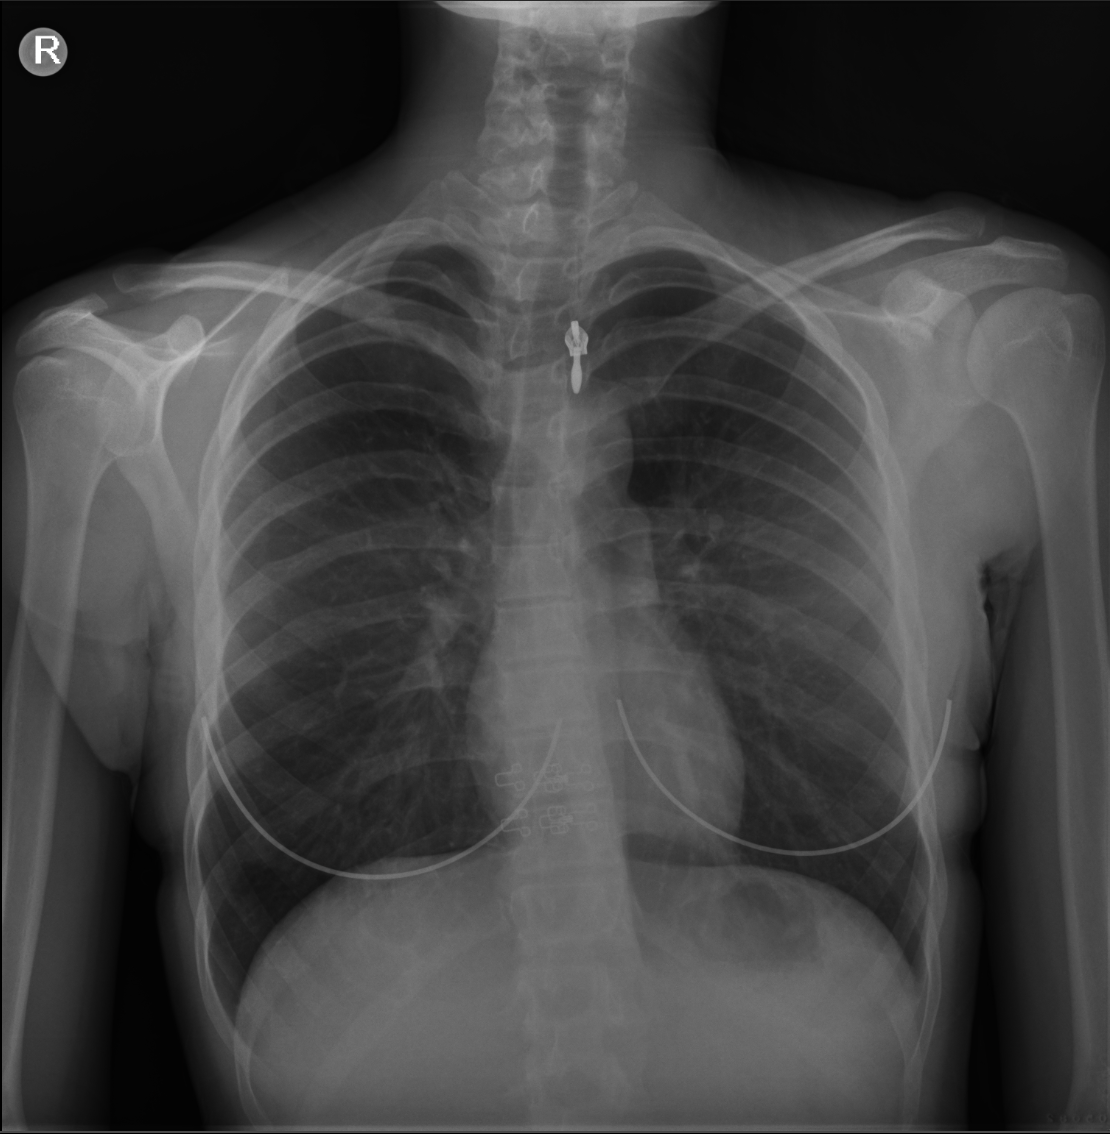

Postroanterior akciğer grafisi 1 yıl önceki akciğer grafisi ile karşılaştırıldığında sağ üst mediastende genişleme görüldü (resim 2)

| 17.11.2023 | 21.11.2024 |

Resim 2: 2024 yılında çekilen akciğer grafisinde 1 yıl önce çekilen grafide görülmeyen sağ üst mediastende genişleme.